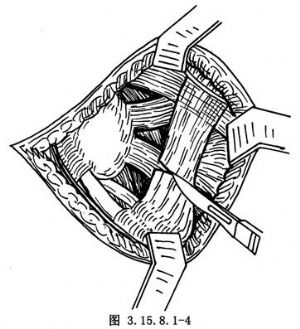

切开皮肤、筋膜组织,不要做皮下浅层分离,防止皮肤坏死。沿切口方向切开踝前十字韧带(图3.15.8.1-4),切口下方的腓骨长短肌腱向下牵拉,将伸趾短肌自跟骨前外侧起点剥离,向远侧翻转,显露跗骨窦,其内有脂肪组织是距跟关节标志(图3.15.8.1-5),清除后切断跟距间韧带,显露距(下)跟关节(图3.15.8.1-6)。在切口上方向前拉开伸趾长肌,在跟骨前即跟骰关节,距骨远端即距舟关节,切开关节囊,足内翻、内收,三个关节都能清楚显露(图3.15.8.1-7)。